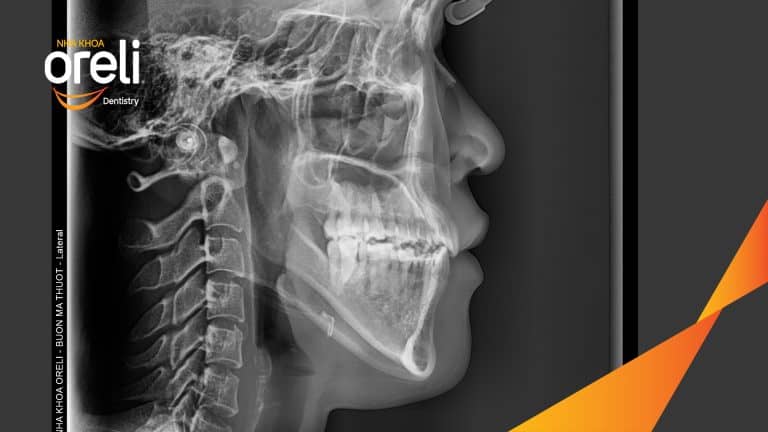

Niềng răng lệch khớp cắn tại Buôn Ma Thuột – Hành trình thay đổi nụ cười tại Nha khoa Oreli Niềng răngMóm Xem thêm